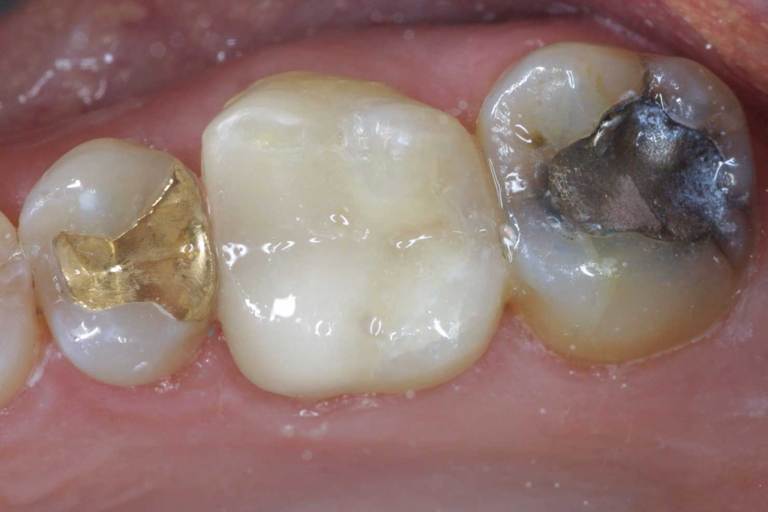

Tooth-colored fillings, white fillings and composite resin fillings are all names for the high-strength, natural-looking fillings that can be placed today instead of silver or gold (also known as amalgam fillings). No matter what the name, Myers Pediatric Dentistry & Orthodontics will know just what you're talking about when referring to this natural-looking filling.

Composite fillings are today's modern filling choice. They are made to match your tooth's natural color to make them virtually invisible to notice and are placed onto the tooth by bonding the filling material to the tooth so they do not have the unlikely chance of falling off. Many patients choose to replace their old silver and gold fillings with composite fillings.

White fillings are made from a high-strength composite resin that can be easily color-matched to your natural tooth making it nearly invisible to you and anyone else. Unlike silver and gold fillings, composite tooth-colored fillings actually bond to the tooth which means they support the surrounding tooth structure, which helps to prevent breakage and insulate the tooth from excessive temperature changes. You are much less likely to have a composite filling fall out which is a common issue with metal fillings.